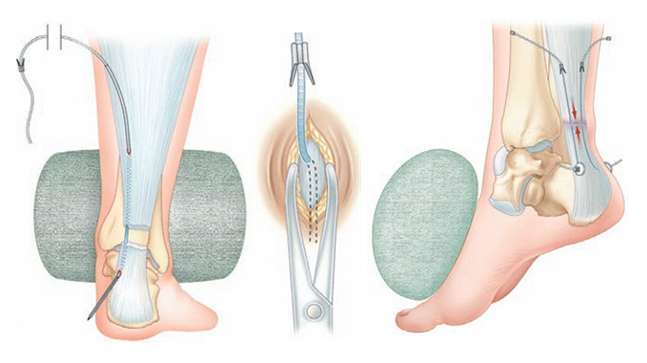

Les différentes réparations du tendon d'Achille ?

Lésion récente

en plein corps tendineux

Lésion récente

en zone myotendineuse

Lésion ancienne

chirurgie reconstructrice

Technique TENOLIG